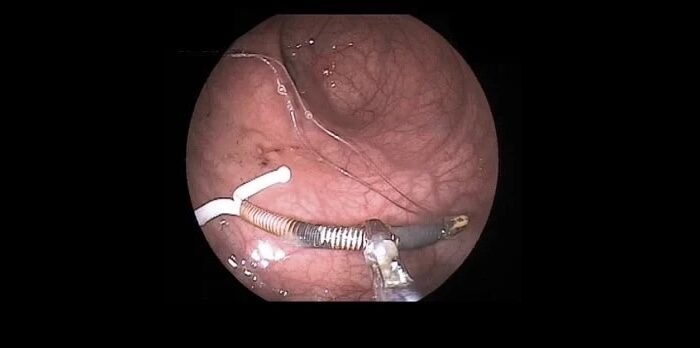

- Histeroscopia diagnóstica y terapéutica.

- Cirugías ginecológicas ambulatorias (ej. extirpación de quistes, miomas, lesiones benignas).